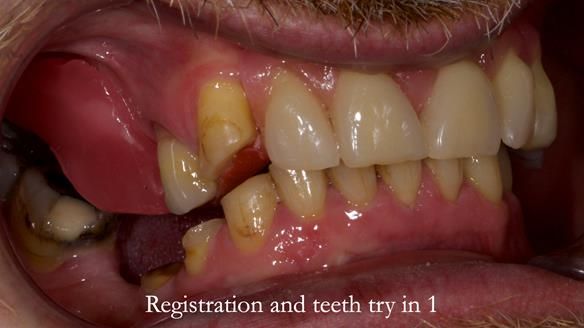

Keith’s case was one of the most challenging and rewarding cases I’ve treated this year. This 64 year old man presented with ill-fitting acrylic partial dentures that lacked stability, retention, and aesthetics. They constantly broke. He had lost the upper front teeth in a road traffic accident in his early 20s. The unopposed teeth had erupted, taking up space. After careful planning, we made a durable, metal-based upper partial denture/splint to address his dental concerns. He loved the outcome.

1. Denture design: A custom cobalt-chromium framework was Scandinavian-designed to maximise stability, protect the remaining teeth, and allow for future additions if needed.

Keith’s denture incorporated a Duracetal shell clasp on upper right first premolar (Myerson), which are designed to be virtually visible, providing a more aesthetic solution while enhancing patient comfort. The Scandinavian-inspired approach, based in modern removable prosthodontic techniques, ensured the denture was not only durable but also visually pleasing. Additionally, the design was carefully planned to allow for future modifications, ensuring that if Keith loses additional teeth, the denture can be adapted rather than replaced entirely.

I also used the Dahl concept to re-establish the occlusion upon fitting the RPD, which helped to intrude the lower left canine without needing to grind it too much.